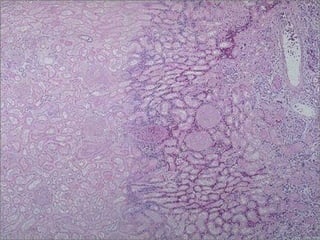

Enzymatic Fat Necrosis

• Results from hydrolytic action of lipases

on fat

• Most often seen in and around the

pancreas; can also be seen in other

fatty areas of the body, usually due to

trauma

• Fatty acids released via hydrolysis react

with calcium to form chalky white areas

 “saponification”

Fat necrosis -- micro

Enzymatic Fat Necrosis •Results from hydrolytic action of lipases on fat • Most often seen in and around the pancreas; can also be seen in other fatty areas of the body, usually due to trauma • Fatty acids released via hydrolysis react with calcium to form chalky white areas  “saponification”